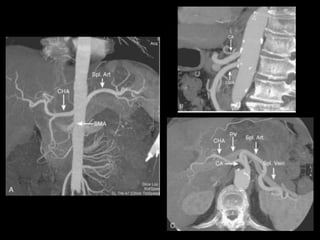

PÂNCREAS-VASOS

AORTA

TRONCO CELÍACO

MESENTÉRICA SUPERIOR

ESPLÊNICA

PANCREÁTICA DORSAL, MAGNA E TRANSVERSA

PANCREATICODUODENAIS SUP E INF

VEIA PORTA